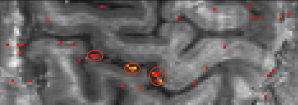

5.) CSF-volume redistribution

The T1-sensitivity in VASO makes it not only sensitive to changes in CBV, but it is actually also believed to be sensitive to volume redistribution of any other T1-compartments too. As such, Piechnik at al., Seong-Gi Kim, the Constable group and Manus Donahue proposed that there might be dynamic change of CSF that can contaminate the VASO contrast. In SS-SI VASO this effect can be accounted for with a balanced combination of TRs and flip angles, as such that CSF and GM have the same baseline signal. In this sequence setup, the VASO signal reflects both: (a) the CBV increase that is compensated with extravascular parenchymal CBV and (b) the CBV increase that is compensated with CSF volume decrease.

With this in mind, it shows an additional channel of potential VASO signal increase (negative VASO voxels): CSF volume reduction that are accompanied the GM volume increase.

Across multiple examples of strong tasks, I never found clear evidence for this to happen. A few examples are shown here. The only exception are global tasks, such as respiration challenges.